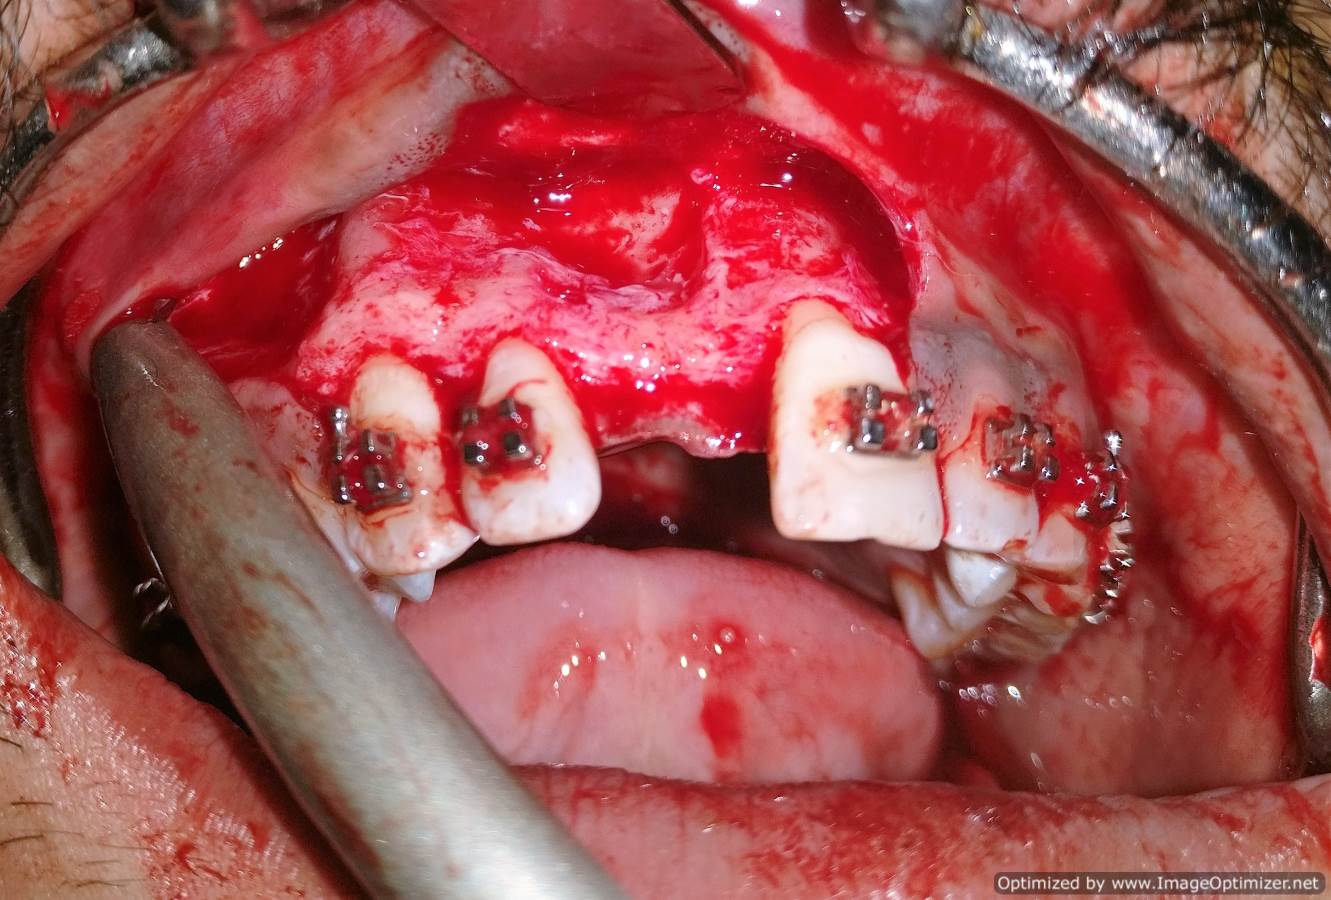

Dental Implant Case Report -03

Home / Case Report / Implant / Dental Implant Case Report -03